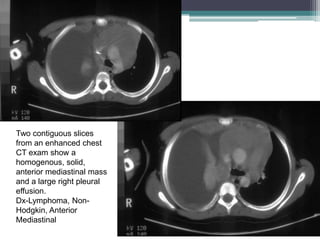

PA and lateral chest films show an

anterior mediastinal mass and a large

right pleural effusion.

Two contiguous slices

from an enhanced chest

CT exam show a

homogenous, solid,

anterior mediastinal mass

and a large right pleural

effusion.

Dx-Lymphoma, Non-

Hodgkin, Anterior

Mediastinal